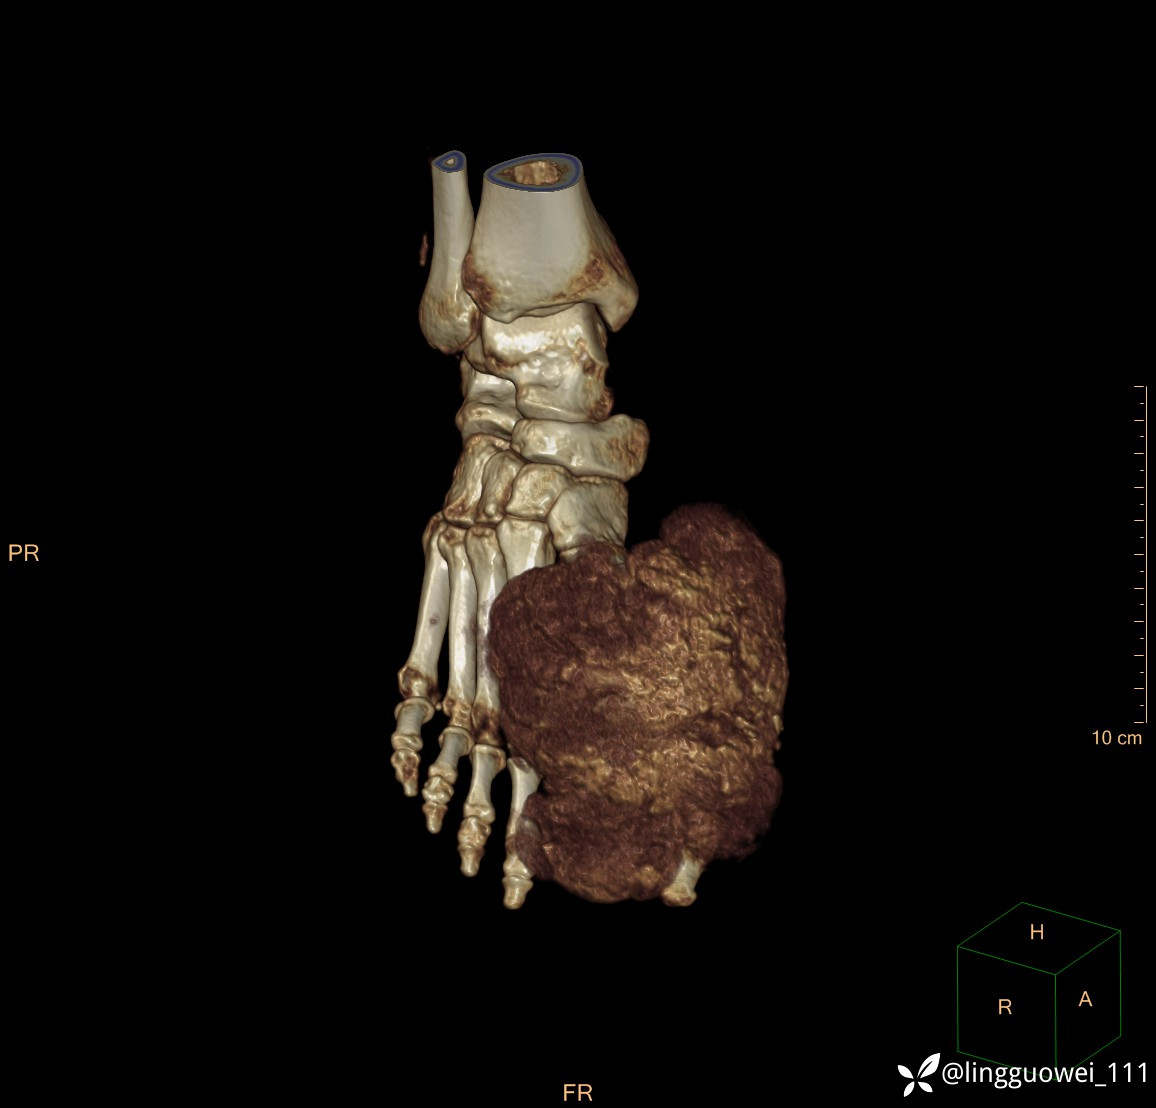

28岁男性,工作中遇到的足部最大的肿块,已补充临床资料。

28岁男性,足部肿块逐渐增大2年。能找到病因吗?

患者于2年余前高嘌呤饮食及大量饮酒后出现全身多处关节痛风石,以右足第一跖趾关节和右手为显,局部红肿热痛反复发作,自行口服药物后可缓解(药物可疑为强的松、双氯芬酸钠等,具体不详)。2年来右足痛风石明显增大,约10cm*5cm*15cm,局部红肿发热,3天前患者再次大量饮酒后痛风石顶部破溃,可见4cm*3cm皮损,较多白色豆渣样分泌物流出,为求进一步治疗来诊,门诊诊断为“右足痛风石破溃伴感染”, 收住院拟手术治疗,患者起病以来,无发热,精神佳、胃纳好、睡眠佳,大小便正常。

专科检查:右足外观畸形,足背部可见巨大痛风石形成,痛风石大小约10cm*5cm*15cm,局部皮肤红肿发热,痛风石顶部破溃,可见4cm*3cm皮损及白色豆渣样分泌物流出;痛风石界限清,质偏硬,局部触及波动感,无压痛,移动度差。右足踇趾及第2趾被痛风石压迫,关节活动受限。肢端血运、感觉无异常。 右手稍肿胀,2-5指背侧可见多发痛风石形成,最大者约花生米大小,皮肤完整未破溃,痛风石界限清,质偏硬,局部触及波动感,无压痛,移动度差。